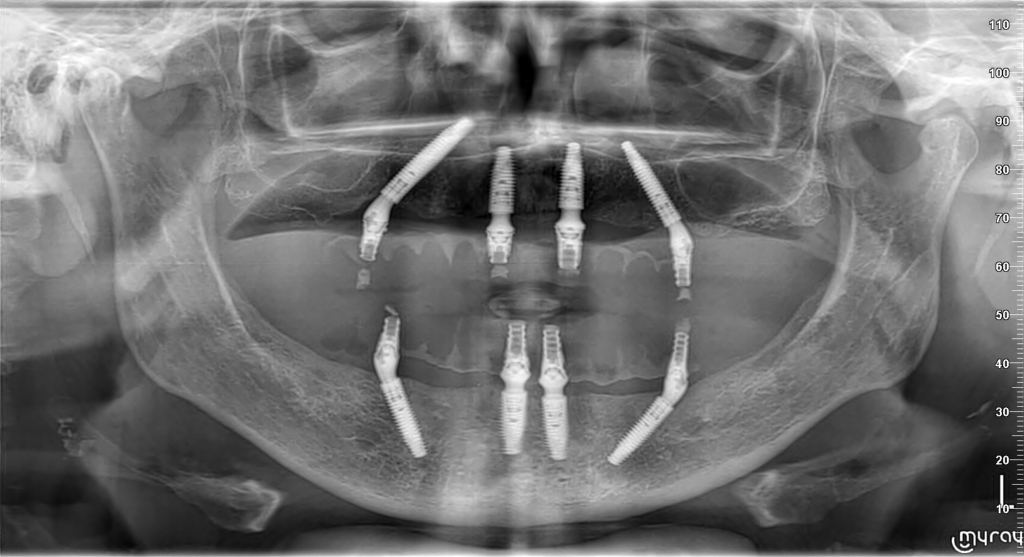

Rješenje potpune bezubosti, kao alternativa mobilnoj potpunoj protezi, su fiksni zubi na 4, 5 ili 6 implantata ovisno i kvaliteti kosti i funkcijskoj potrebi pojedinog pacijenta.

Standardni pristup je postavljanje četiri implantata u gornju i četiri implantata u donju čeljust (All-on-4) te izrada privremenih zuba unutar 24 sata od zahvata koji ostaju u pacijentovim ustima 6 mjeseci do potpune oseointegracije implantata nakon čega se izrađuje trajni most.

Trajni most se sastoji od titanske konstrukcije sa cirkonskim, kompozitnim ili akrilatnim zubima, ovisno o indikaciji.